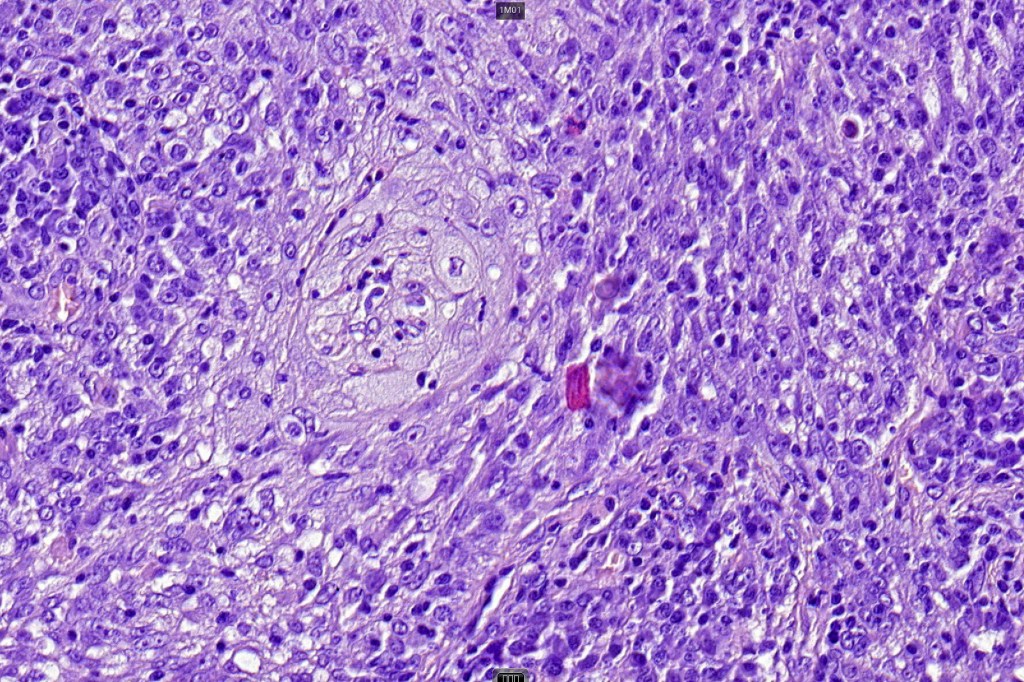

•Biphasic tumor combining squamous cell carcinoma and adenocarcinoma; the latter showing ductal and glandular differentiation

•Glands are lined by cuboidal to columnar epithelium

•Intracytoplasmic lumina sometimes evident

•Glandular foci show mucin

•Variable pleomorphism & mitotic activity but can be marked